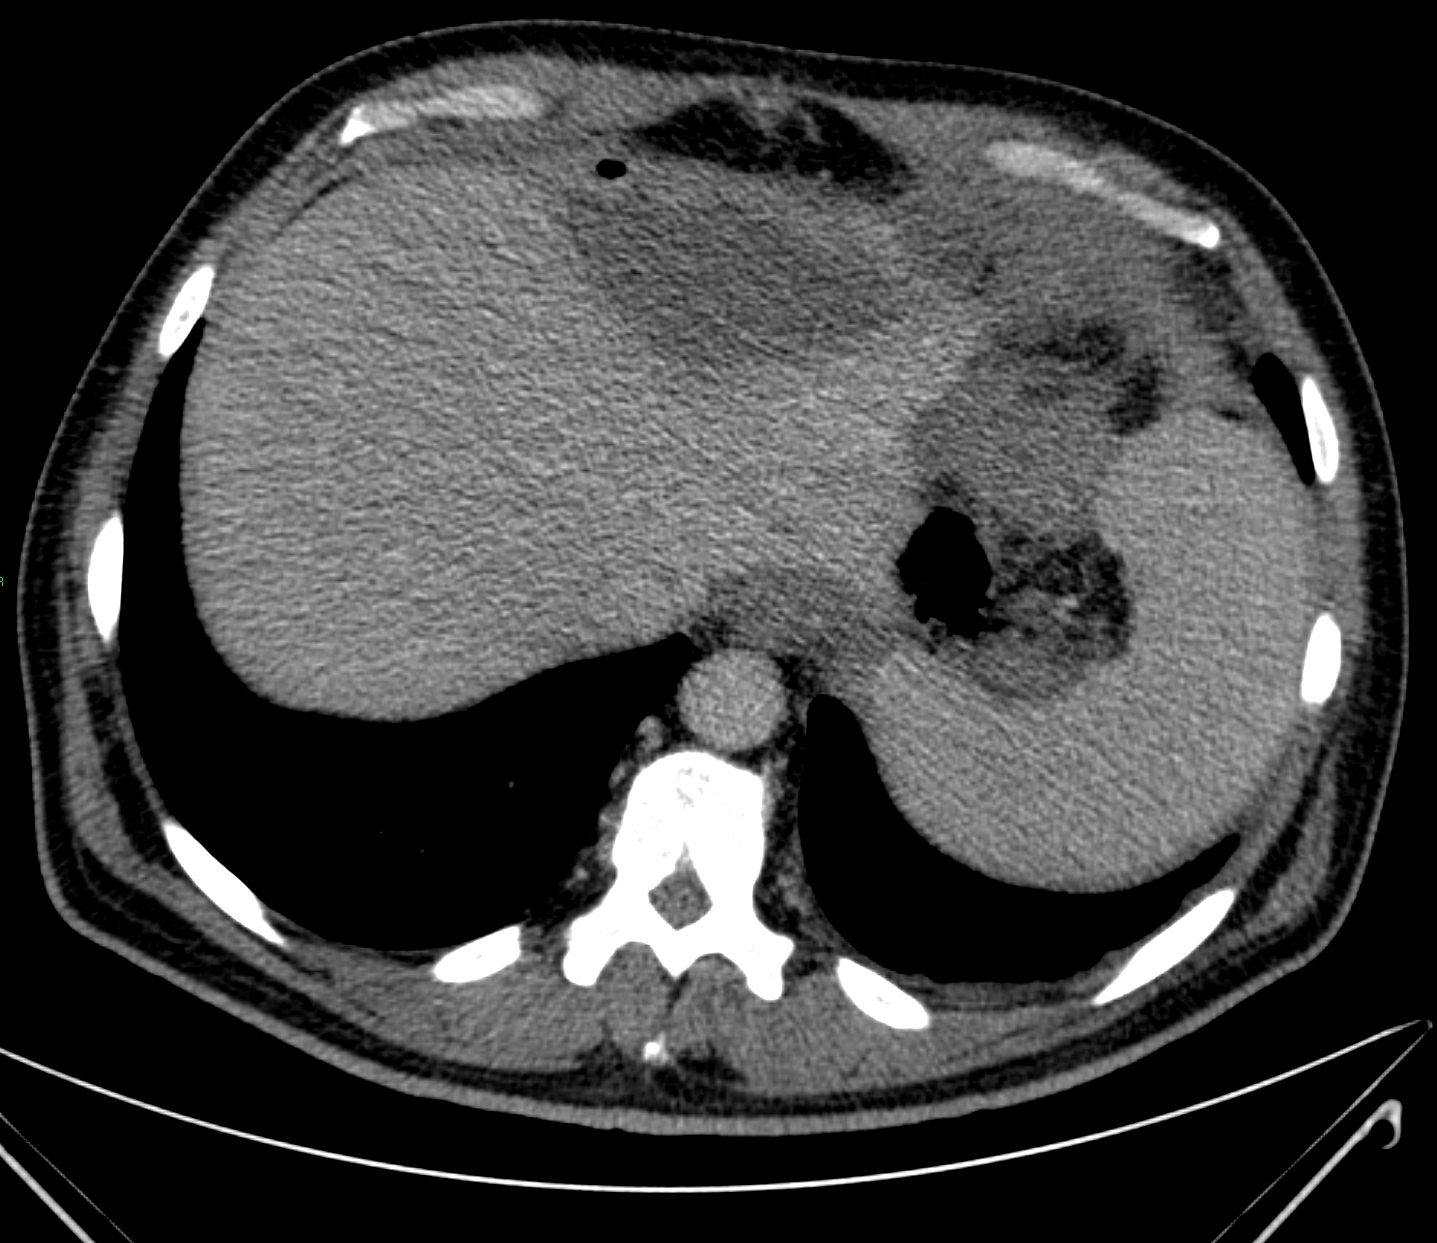

The triglicerides accumulate in the hepatocytes. The parenchyma reflectivity and the beam absorption increases (Figure 12). The increase of the reflectivity is usually homogeneous, rarely inhomogeneous.

Figure 12: Fatty liver, small HCC, distal attenuation